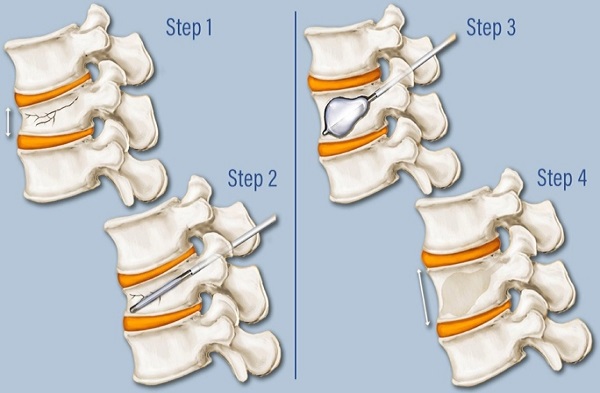

Kyphoplasty or Vertebroplasty

Spinal compression fractures, often caused by osteoporosis, trauma, or tumors, can lead to